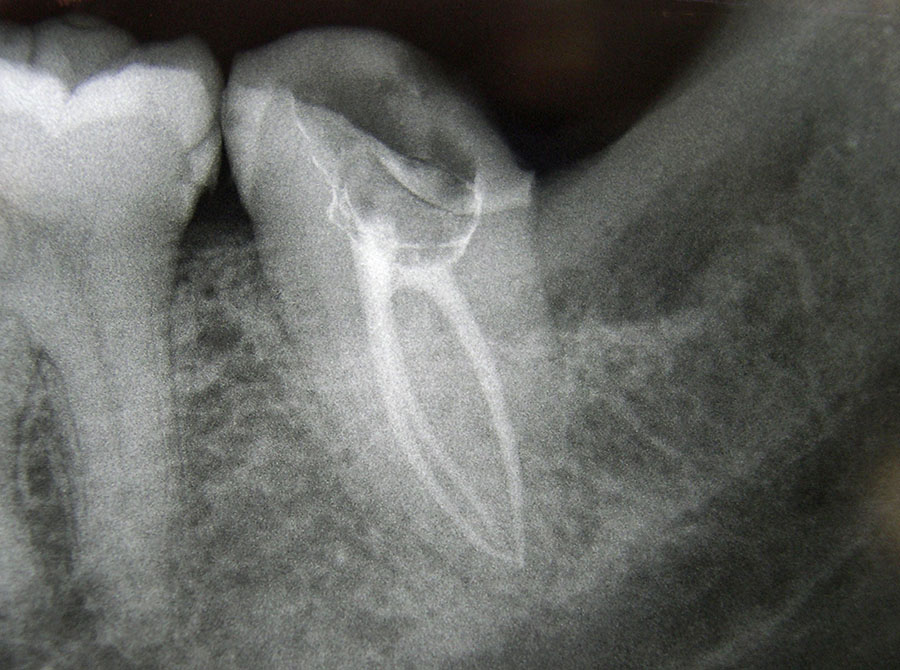

Im Inneren jedes Zahnes befindet sich ein kanalförmiger Hohlraum, in dem der Nerv und die versorgenden Blutgefäße verlaufen.

Bei einer Zerstörung der harten Außenschale, z.B. durch eine traumatische Zahnverletzung (Sturz, Schlag, etc.) oder durch eine tiefe Karies kann der Nerv im Inneren verletzt und bakteriell entzündet werden.

Ist der Nerv im Inneren eines Zahnes erkrankt, muss er im Rahmen einer Wurzelkanal-behandlung schnellstmöglich entfernt werden.

Sonst kann es durch fortschreitende bakterielle Zersetzungsprozesse zu einer Entzündung an der Wurzelspitze des Zahnes kommen, die sich in den Knochen ausbreitet.

Bei einer Wurzelkanalbehandlung wird (meist unter Anästhesie) das erkrankte Nervgewebe entfernt, der Wurzelkanal mit desinfizierenden Lösungen gespült, schrittweise im Durchmesser aufbereitet, mit antibakteriellen Einlagen bis zur Schmerzfreiheit versorgt und schließlich bakteriendicht abgefüllt. Dies kann mehrere Behandlungssitzungen erfordern.

Entscheidend für den Langzeiterfolg einer Wurzelkanalbehandlung ist die exakte Füllung des gesamten Wurzelkanals bis zur Wurzelspitze. Daher verlassen wir uns hier nicht nur auf Röntgenbilder, sondern messen mit modernen Zusatzgeräten elektronisch die Länge jedes Wurzelkanals .Die Aufbereitung der Kanäle erfolgt teils von Hand, teils maschinell mit speziell dafür entwickelten, drehmomentbegrenzten Motoren und hochflexiblen Einmal-Feilen. Vor der endgültigen Wurzelfüllung wird bei uns jeder Wurzelkanal laser-sterilisiert, d.h. evtl. noch vorhandene Bakterien werden durch Zufuhr hochenergetischen Laserlichts über flexible Glasfasern abgetötet.